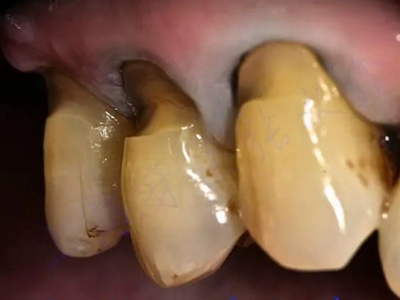

楔状缺损是一种非龋性牙颈部慢性损伤,是指发生在牙齿唇、颊面颈部的慢性硬组织缺损。典型缺损由两个夹面组成,口大底小,呈楔形。楔状缺损多发生于中老年人,主要原因是刷牙不当,防治措施是调整咬合关系,改善刷牙方法,配合相应的治疗。

楔状缺损与年龄相关,即年龄越大,缺损越重,患者多有横刷牙习惯,患牙为多颗甚至全口,常以口角附近的牙齿(尖牙、前磨牙)为重。典型表现为牙颈部缺损,呈楔形,由两个夹面组成,口大底小,缺损处质地坚硬,表面光滑,边缘整齐,无染色,轻微泛黄常为牙齿本色,严重时可导致牙髓腔暴露甚至牙齿横向折断,根据缺损深浅不同,可伴有牙齿敏感甚至疼痛。

不正确的刷牙方法,尤其是横刷法是发生楔状缺损的主要原因,因为牙颈部结构比较薄弱,易发生磨损。另外,颊面牙颈部是咬合应力集中区,长期的咀嚼压力使牙体组织疲劳,应力集中区出现破坏,也会造成楔状缺损。龈沟内酸性渗出物,也与楔状缺损的发生有关。

如果楔状缺损不深、症状不明显,可以不处理,有过敏症状可进行脱敏治疗。楔状缺损较深者可行充填修复。缺损达到牙髓腔,导致牙髓感染、根尖周病或牙齿横折者,可进行根管治疗、拔除患牙,再进行修复。平时要采取正确的刷牙手法,例如巴氏刷牙法,避免咬硬物。必要时通过正畸、修复等方法调整咬合关系。